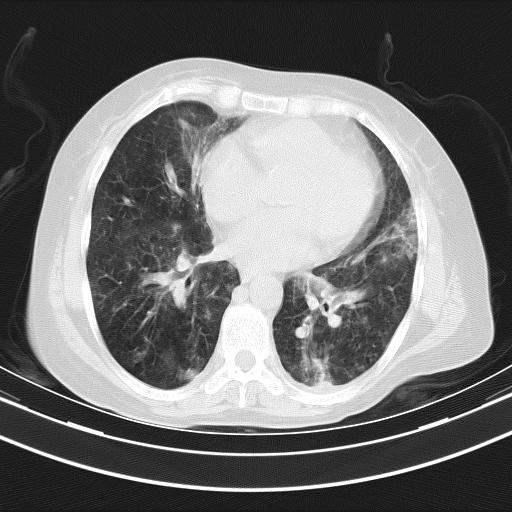

老年女性,嗜睡3天,意识模糊。轻咳,无发热。

两肺慢支炎伴感染,左侧胸腔积液。纵膈及双侧肺门淋巴结肿大建议复查。

双肺多发淡片影,毛玻璃影,,支持支气管肺炎,,建议血气找原因,,嗜睡是否肺性脑病?有没有慢支病史?

双肺炎症,建议抗炎治疗后复查,见过几个老年肺炎病例,没有发烧、咳嗽症状,直接以昏迷就诊。

1)两肺感染性病变;建议抗炎治疗后复查。2)纵隔淋巴结肿大。3)左侧胸腔积液。